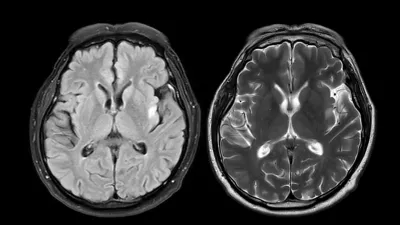

MRI brain scan axial T1W for detect Brain diseases sush as stroke disease, Brain tumors and Infections. / Foto: Mr.suphachai Praserdumrongchai